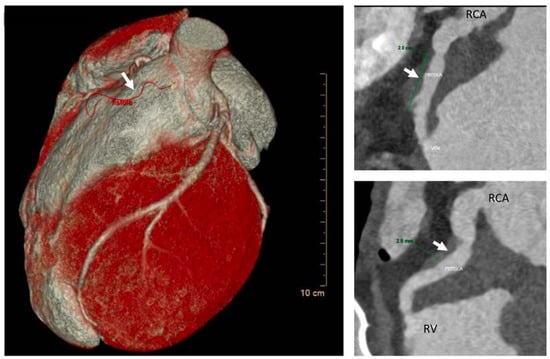

2. Case Description